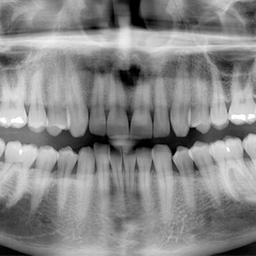

Нарийн оношилгоо

X-ray-ээр шүдний цоорхойн хүрээ болон гүнзгий байдлыг нарийн тодорхойлно.